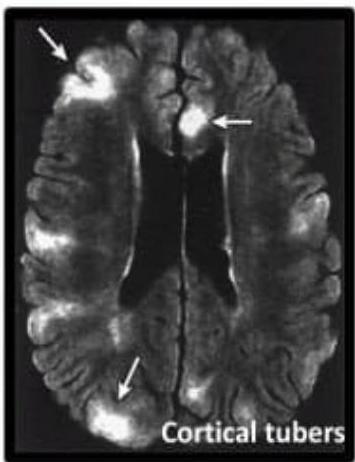

- Cortical Tubers: Brain lesions (Cortical dysplasias).

Cortical tubers: